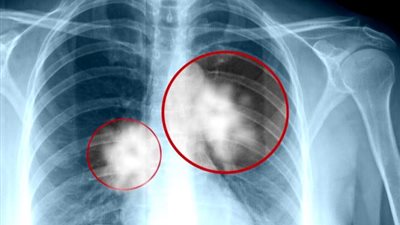

الجمعية الأمريكية لأبحاث السرطان تتوصل لأحدث دواء لأورام الرئة

توصلت دراسة جديدة تم عرضها في اجتماع الجمعية الأمريكية لأبحاث السرطان في شيكاغو، إلى دواء جديد يعمل على دعم الجهاز المناعي، مما يساعد في إطالة عمر المرضى المصابين بسرطان الرئة في الحالات المتقدمة عند ...